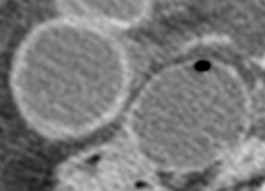

1º) – Engrosamiento de la pared intestinal:

La pared normal mide entre 3 y 5 mm. El engrosamiento es el hallazgo más observado en la isquemia mesentérica, pero también es el más inespecífico. Se produce por edema mural, hemorragia o sobreinfección de la pared intestinal.

Este hallazgo es más acusado en la colitis isquémica y la isquemia mesetérica reversible. En caso de infarto transmural (no reversible), puede existir un adelgadzamiento de la pared intestinal («paper thin wall») lo cual es debido a la pérdida de tono muscular y de volumen de los vasos parietales. En asas sobredistendidas, grosores de 3 mm pueden ser significativos de isquemía. En contracciones espásticas del colon, puede exitir más de 5 mm de grosor.

Por ello, confirmarmos que el engrosamiento mural es un signo poco específico y correlaciona mal con el grado de severidad.

3º) -Atenuación:

TC sin contraste: la pared hipodensa indica edema de pared. La pared hiperdensa es causada por hemorragia intramural.

TC con contraste: el realce de contraste ausente o disminuido de la pared es un hallazgo muy específico de isquemia (aunque no sensible) e indica infarto intestinal (no reversible).

Otro signo de isquemia es el halo o apariencia de diana de la pared. Se produce por la hiperemia y la hiperperfusión asociado con edema mural.

Tambien se puede observar aumento de realce de la pared por aumento de la presión venosa capilar e ingurgitación venosa. Es un signo precoz de isquemia e indica reversibilidad.